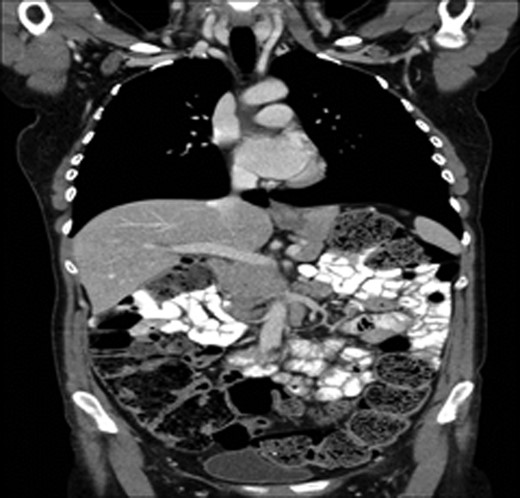

A 43-year-old female, 10 weeks postpartum, underwent colonoscopy for bleeding per rectum showing a bulky tumour (Fig. 1) in the rectum at 5 cm. Histologically poorly differentiated adenocarcinoma of the rectum (Fig. 2) T3N1Mo. Underwent laparoscopic loop ileostomy formation for impending bowel obstruction. Bloods showed Hemoglobin13.6 g/dL, Bilirubin 10umol/L, CEA 3.6 ng/mL. MRI pelvis (Fig. 3a and b) showed locally advanced annular neoplasm of mid and upper rectum. CT TAP (Fig. 4) reported no distant metastasis. She had neoadjuvant chemoradiothreapy with poor response. Post chemotherapy she noticed a lump in her right breast and axilla. Breast mammogram (Fig. 5a) showed 26 mm lesion in the right breast at 10 o'clock position and ultrasound showed 27 mm lesion in right axilla. Core biopsy (Fig. 6) reported signet ring morphology. The tumour stained positive with CK20, CDX-2 and CEA. There was no staining with CK7, ER, PR or Her-2. The rectal biopsy specimen, also analysed for KRAS status, was KRAS/NRAS/BRAF negative. She is being followed up by oncology with FOLFOX+Panitumumab.

(a) Mammogram post-neoadjuvant chemoradiothreapy showing right breast mass. (b) CT TAP pos-tneoadjuvant chemoradiothreapy showing enlarged right axillary lymph node.